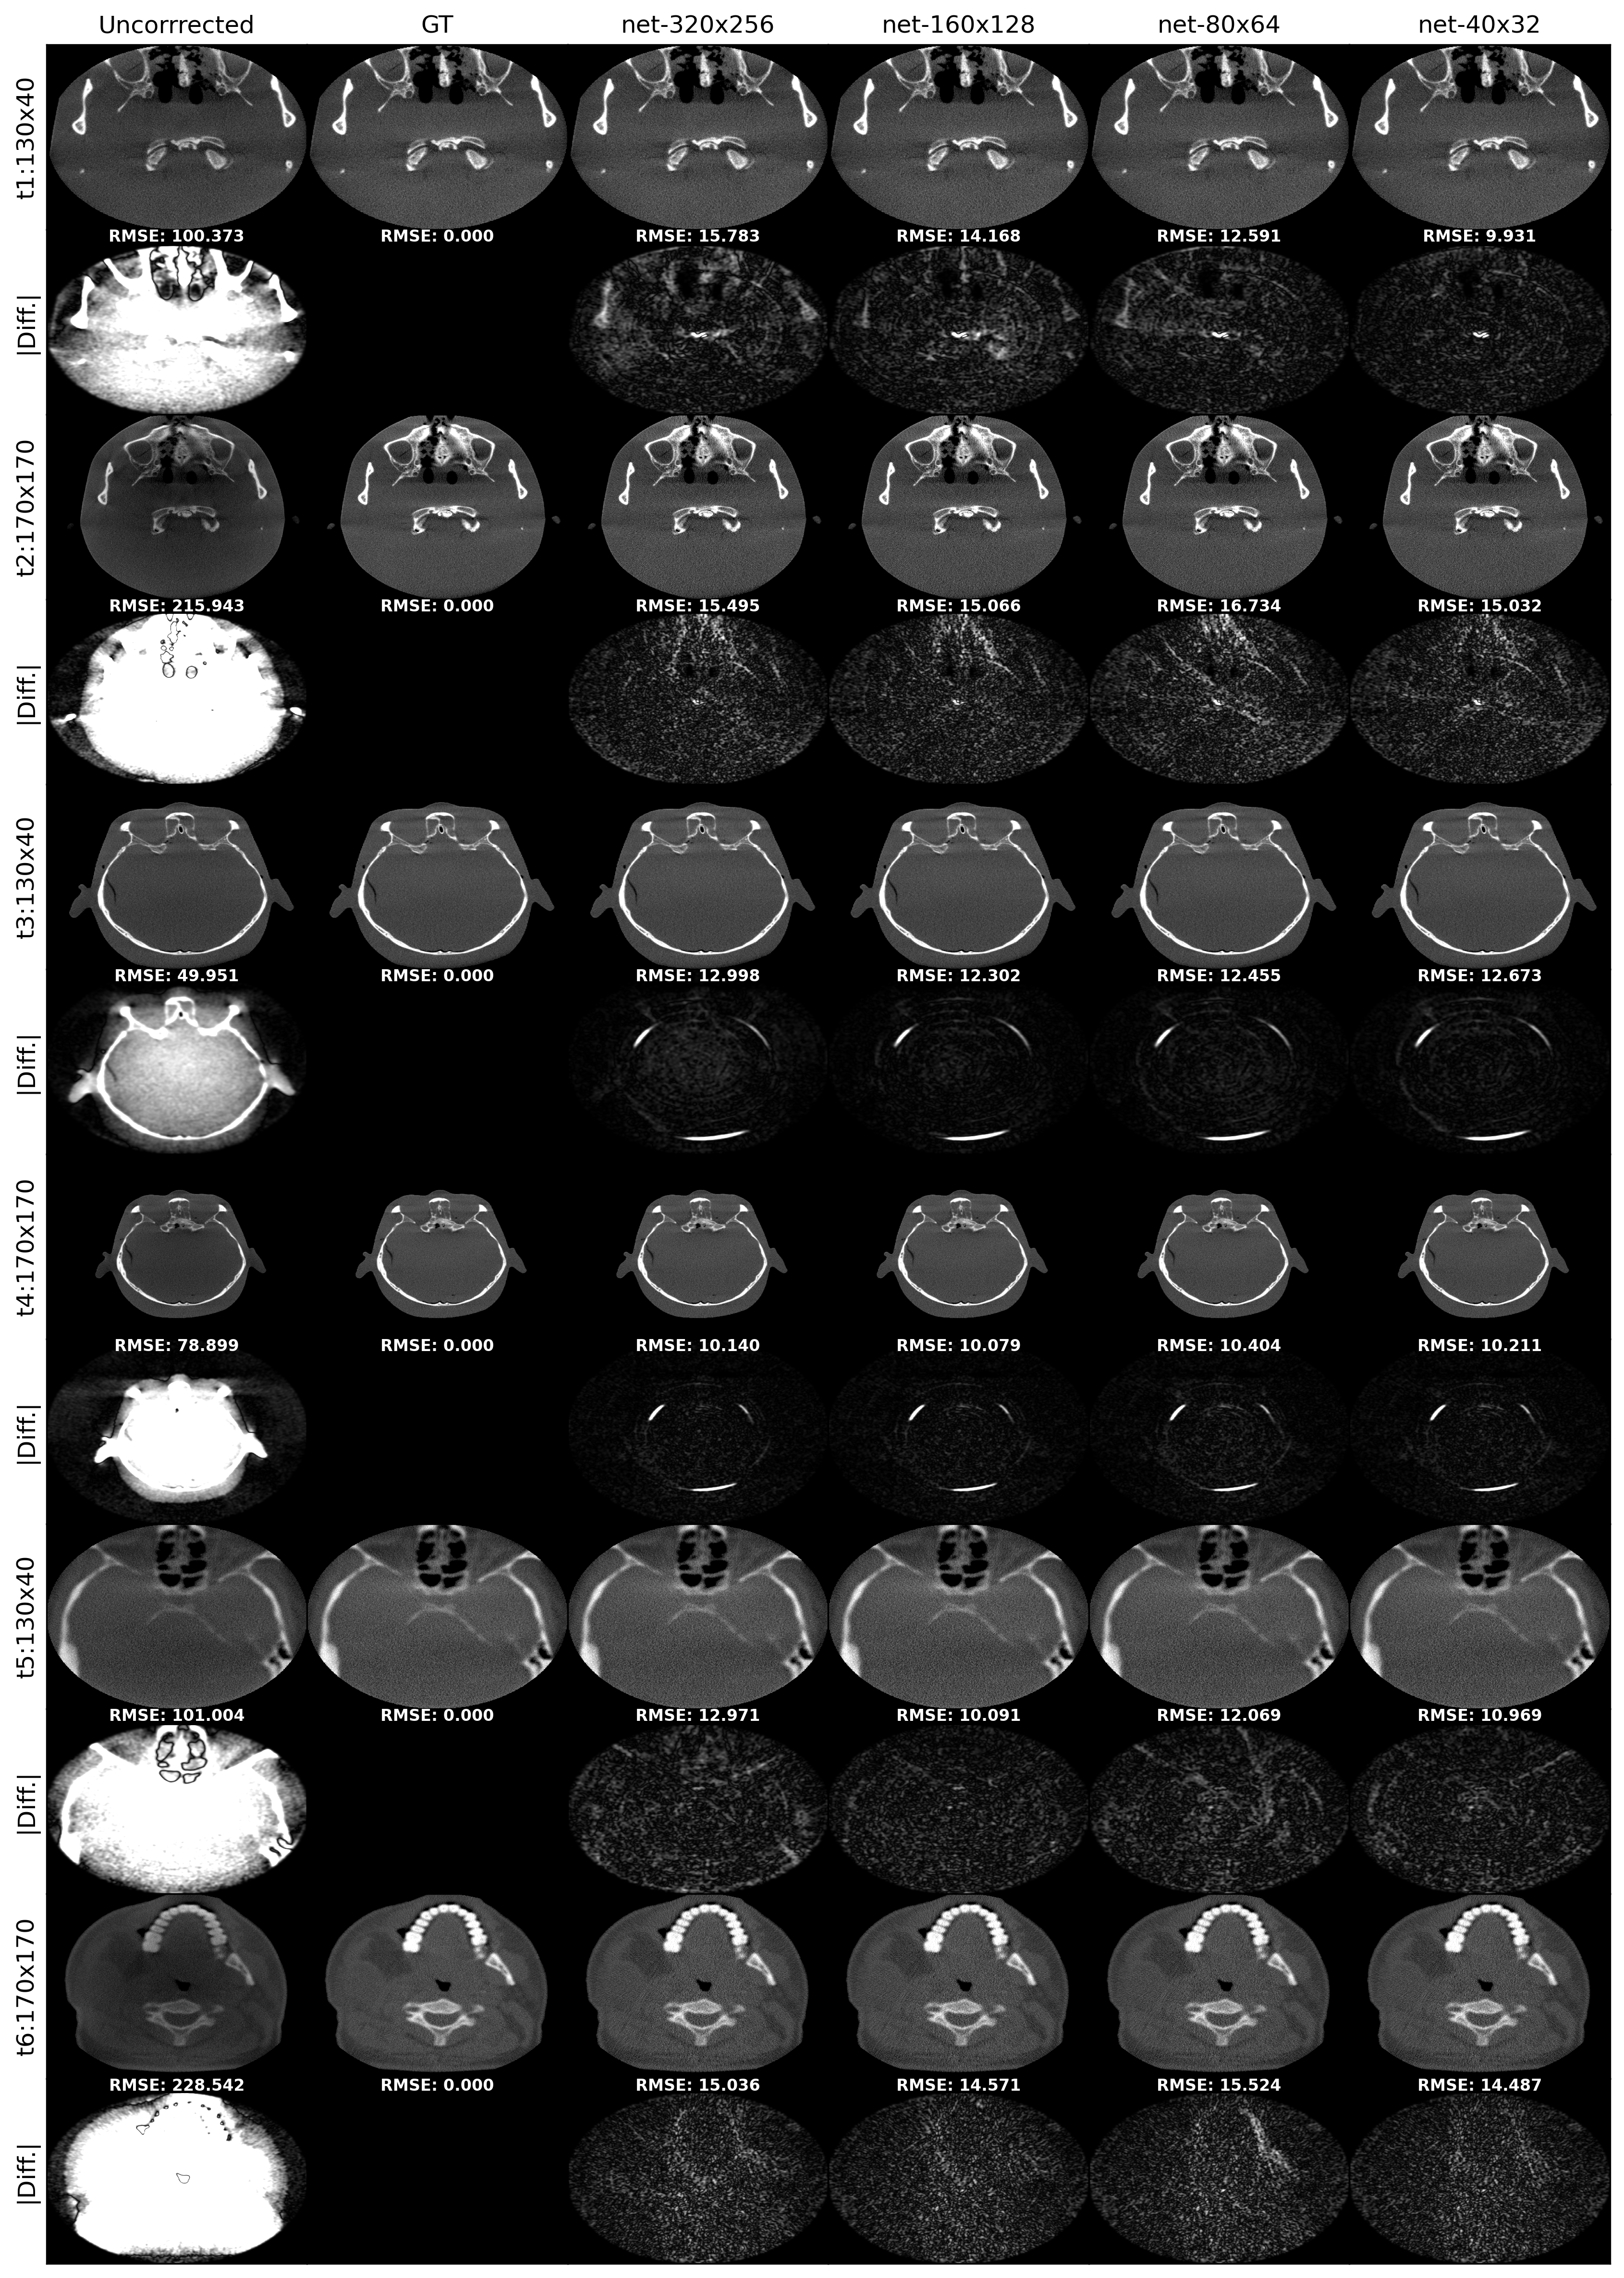

Refer to caption

Figure 4: Example of the reconstructed axial images after scatter correction along with the uncorrected, ground truth, and the absolute difference from the ground truth images. t:1–6 corresponds to six different test images. The display window center and width of the absolute difference is 50 HU.

3.4 Scatter correction on the simulated reconstructions

Table 3 presents the RMSE (HU) for 30 different FOM sizes calculated for the reconstructed images. The lowest average RMSE was 8.85 ± 2.92, achieved by the net-160×128160\times 128, closely followed by the net-40×3240\times 32 with an RMSE of 8.96 ± 2.90. The net-320×256320\times 256 performed the worst, with an RMSE of 9.66 ± 2.29, followed by the net-80×6480\times 64 with an RMSE of 9.01 ± 2.92.

Exemplary axial images, corrected with different methods, along with the absolute difference from the corresponding MC-simulated ground truth are shown in Fig. 4. Images with both the maximum 170×170170\times 170 mm and minimum 130×30130\times 30 mm FOMs from three different reconstructions are visualized.